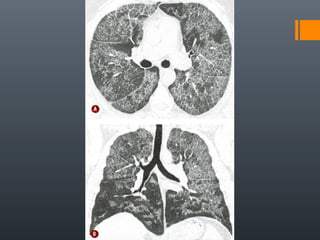

O documento discute vários conceitos radiológicos incluindo consolidação, atelectasia, nódulos, pseudocavidades e padrões intersticiais, fornecendo definições, sinais e diagnósticos diferenciais para cada tópico. Ele também discute a redução da atenuação pulmonar e fornece um link para mais informações.